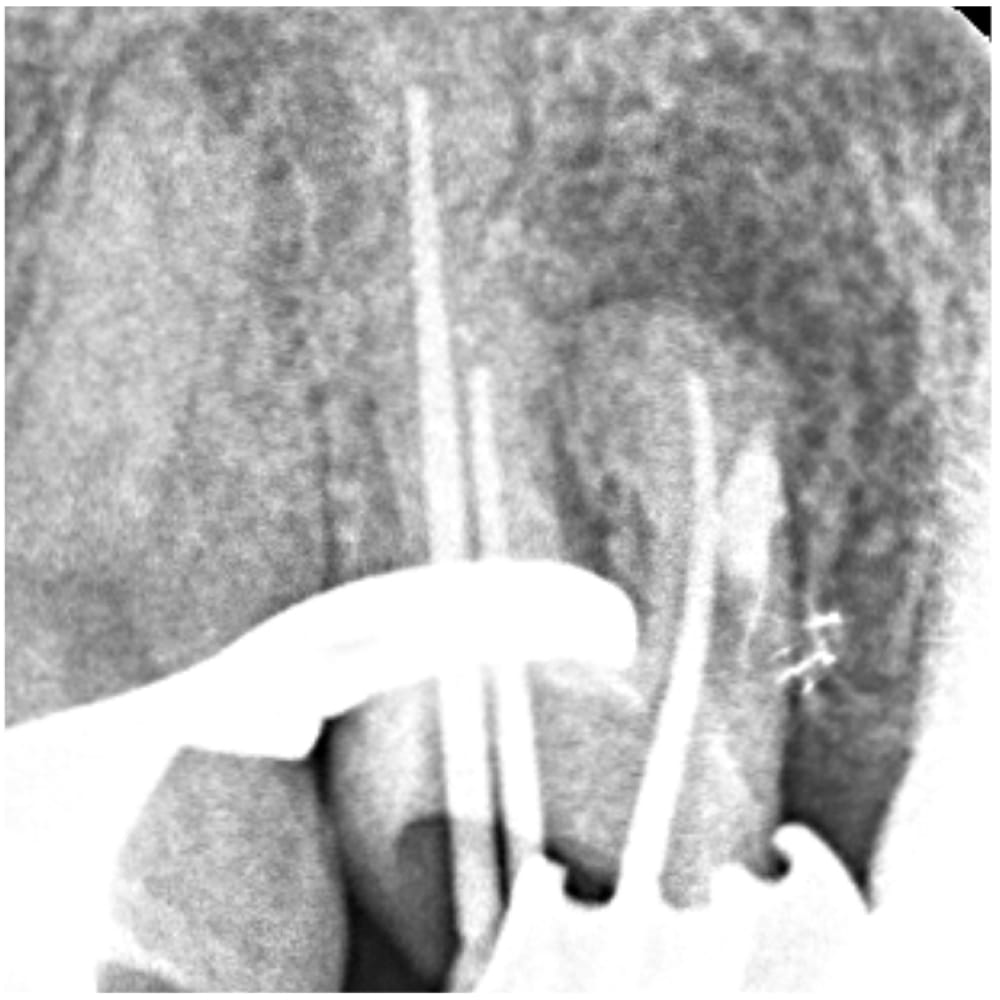

ステップ5

根管充填に使用するガッタパーチャポイントの到達位置の確認です。未処置であった他の根管も、根の先端付近まで器具が届いているのが確認できます。